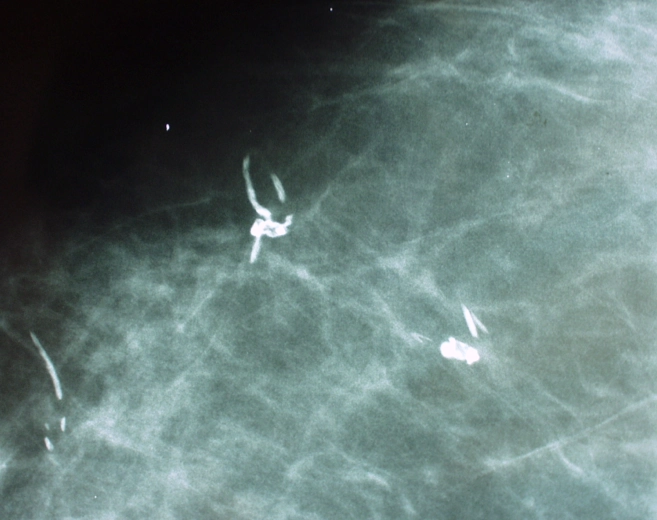

Vôi hóa chỉ khâu (Suture calcification in breast)